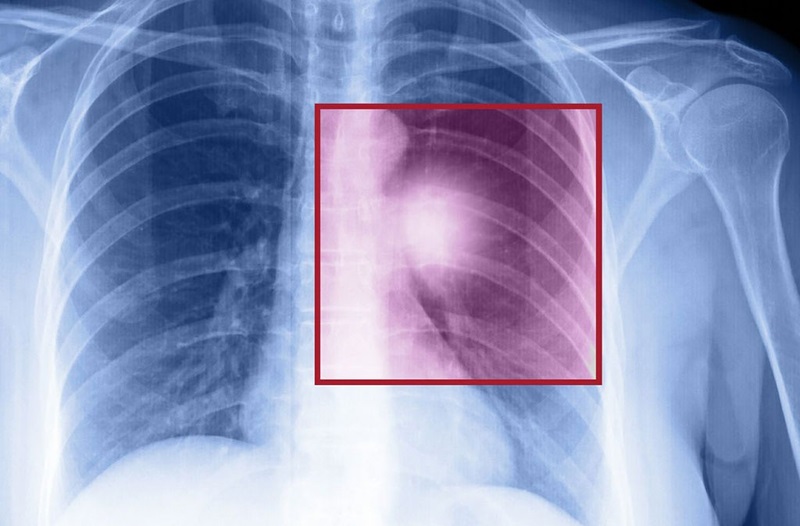

Sinh thiết phổi là kỹ thuật chẩn đoán quan trọng mang lại nhiều giá trị cho các bệnh nhân mắc bệnh lý phổi. Các thủ thuật sinh thiết giúp bác sĩ đánh giá chính xác các bất thường ở phổi của người bệnh. Từ đó, đề ra hướng điều trị phù hợp cho người bệnh.

Sinh thiết phổi là một thủ thuật xâm lấn nhằm lấy mẫu tế bào/ mẫu mô ở phổi ra khỏi cơ thể. Mẫu mô tế bào đó sẽ được quan sát, chẩn đoán nhằm đưa ra kết luận bệnh lý cho bệnh nhân. Trong đó, phát hiện ra các tình trạng như: viêm phổi, khối u phổi, phổi kẽ, viêm phổi quá mẫn,…

sinh thiết phổi Sinh thiết phổi là phương pháp hiệu quả trong xác định tổn thương ở phổi

Với những kết quả bất thường từ phim chụp, bệnh nhân sẽ được chỉ định làm sinh thiết phổi. Các kết quả từ sinh thiết phổi sẽ là căn cứ thuyết phục nhằm chẩn đoán đúng bệnh lý. Trong đó, sẽ làm rõ những thông tin sau:

• Làm rõ những bất thường ở kết quả chụp cắt lớp vi tính.

• Xác định tính chất khối u là u lành tính hay ác tính (trong trường hợp khối u đã hình thành)

• Xác định giai đoạn phát triển của khối u

• Giúp chẩn đoán nguyên nhân tràn dịch màng phổi

• Làm rõ thêm về bệnh lý viêm, nhiễm trùng ở phổi